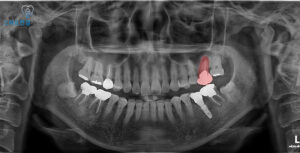

자세히 확인을 하기 위해

파노라마 촬영을 해보았는데요.

해당 치아 뿌리 끝에

염증이 크게 잡혀있는 것을

확인할 수 있었어요.